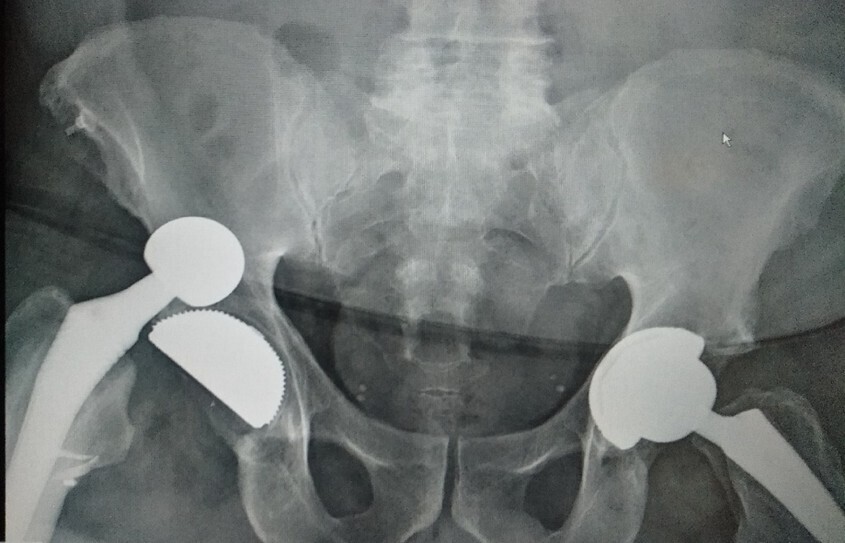

• les interventions prothétiques non conservatrices (fig. 1).

Surveillance et durée de vie d’une prothèse

Une dégradation fonctionnelle tardive peut traduire une évolution de la pathologie initiale ou la dégradation du traitement (descellement de prothèse, arthrose après ligamentoplastie…). Si une prothèse est présente, même en cas de pathologie de voisinage, comme une cruralgie, un bilan radiologique de l’implant doit être effectué.

Les prothèses articulaires doivent être revues à intervalles réguliers car elles peuvent montrer des signes d’usure et/ou un descellement, initialement révélé par des radiographies et conduisant, en l’absence de signes cliniques, à une surveillance plus rapprochée. En cas de signes cliniques et selon l’état général, le changement de prothèse est souvent possible, avec une morbidité actuelle moindre.

La durée de vie d’une prothèse ne peut pas être prédite individuellement. Mais hors complications (infections, fracture…), elle est en moyenne de vingt ans. Cette durée varie en fonction de l’indication initiale, des antécédents locaux et généraux et de l’activité du patient.

La survenue tardive d’une première luxation de prothèse de hanche après un geste banal traduit une usure de la pièce cotyloïdienne, une fracture tardive sur implant céramique ou une altération musculaire des fessiers. Dans ce contexte, une reprise uni- ou bipolaire doit être évoquée, sans attendre une récidive de la luxation.